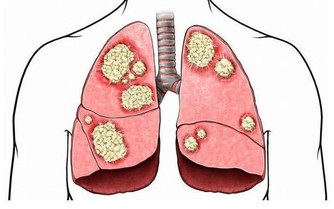

前人云:“癌瘤者,非陰陽正氣所結,乃五臟瘀血濁氣痰滯而成。毒和瘀是人體內的垃圾,時刻都會產生,身體一系列瘀堵,會使臟腑功能失調,氣血不和,濁邪積聚,漸漸積累就變成癌。